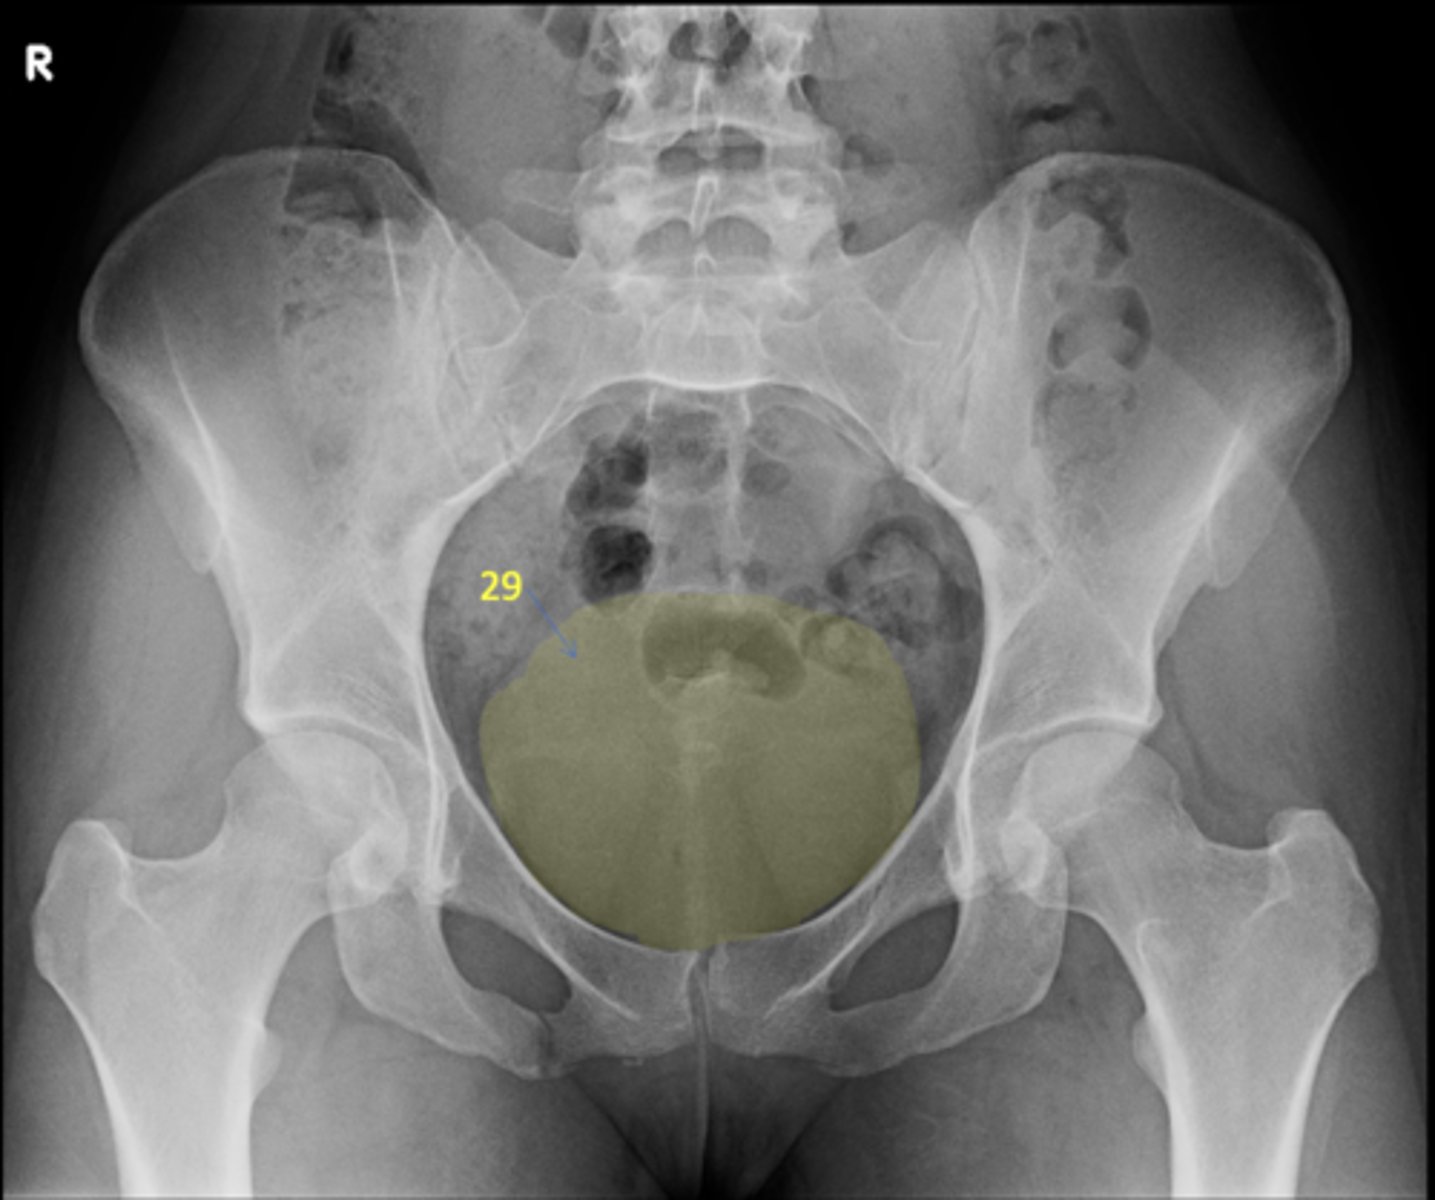

26

New cards

Bladder

ID 29

27

Ascending colon

ID 30

28

Left AP hip

View?